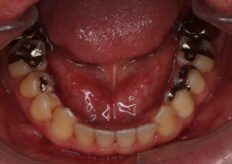

Before

上下の前歯のかみ合わせを診てみますと下の前歯が上の前歯の裏側に当たっている状態でした、

このままでは上の隙間は閉じる事ができないので下の前歯に歯と歯の間にすこし隙間があるので、

この隙間を閉鎖をすることと上の犬歯の後ろに隙間を移動させる事で前方からの審美を良くしました、